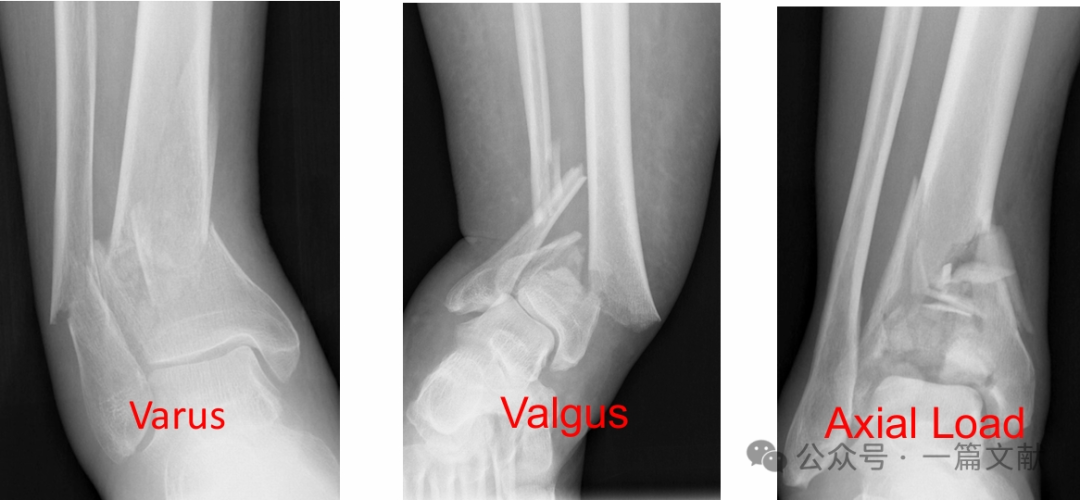

对抗骨折初始移位方向放置接骨板。

内翻畸形 → 内侧支撑

外翻畸形 → 外侧支撑

距骨前/后向移位 → 前/后侧支撑